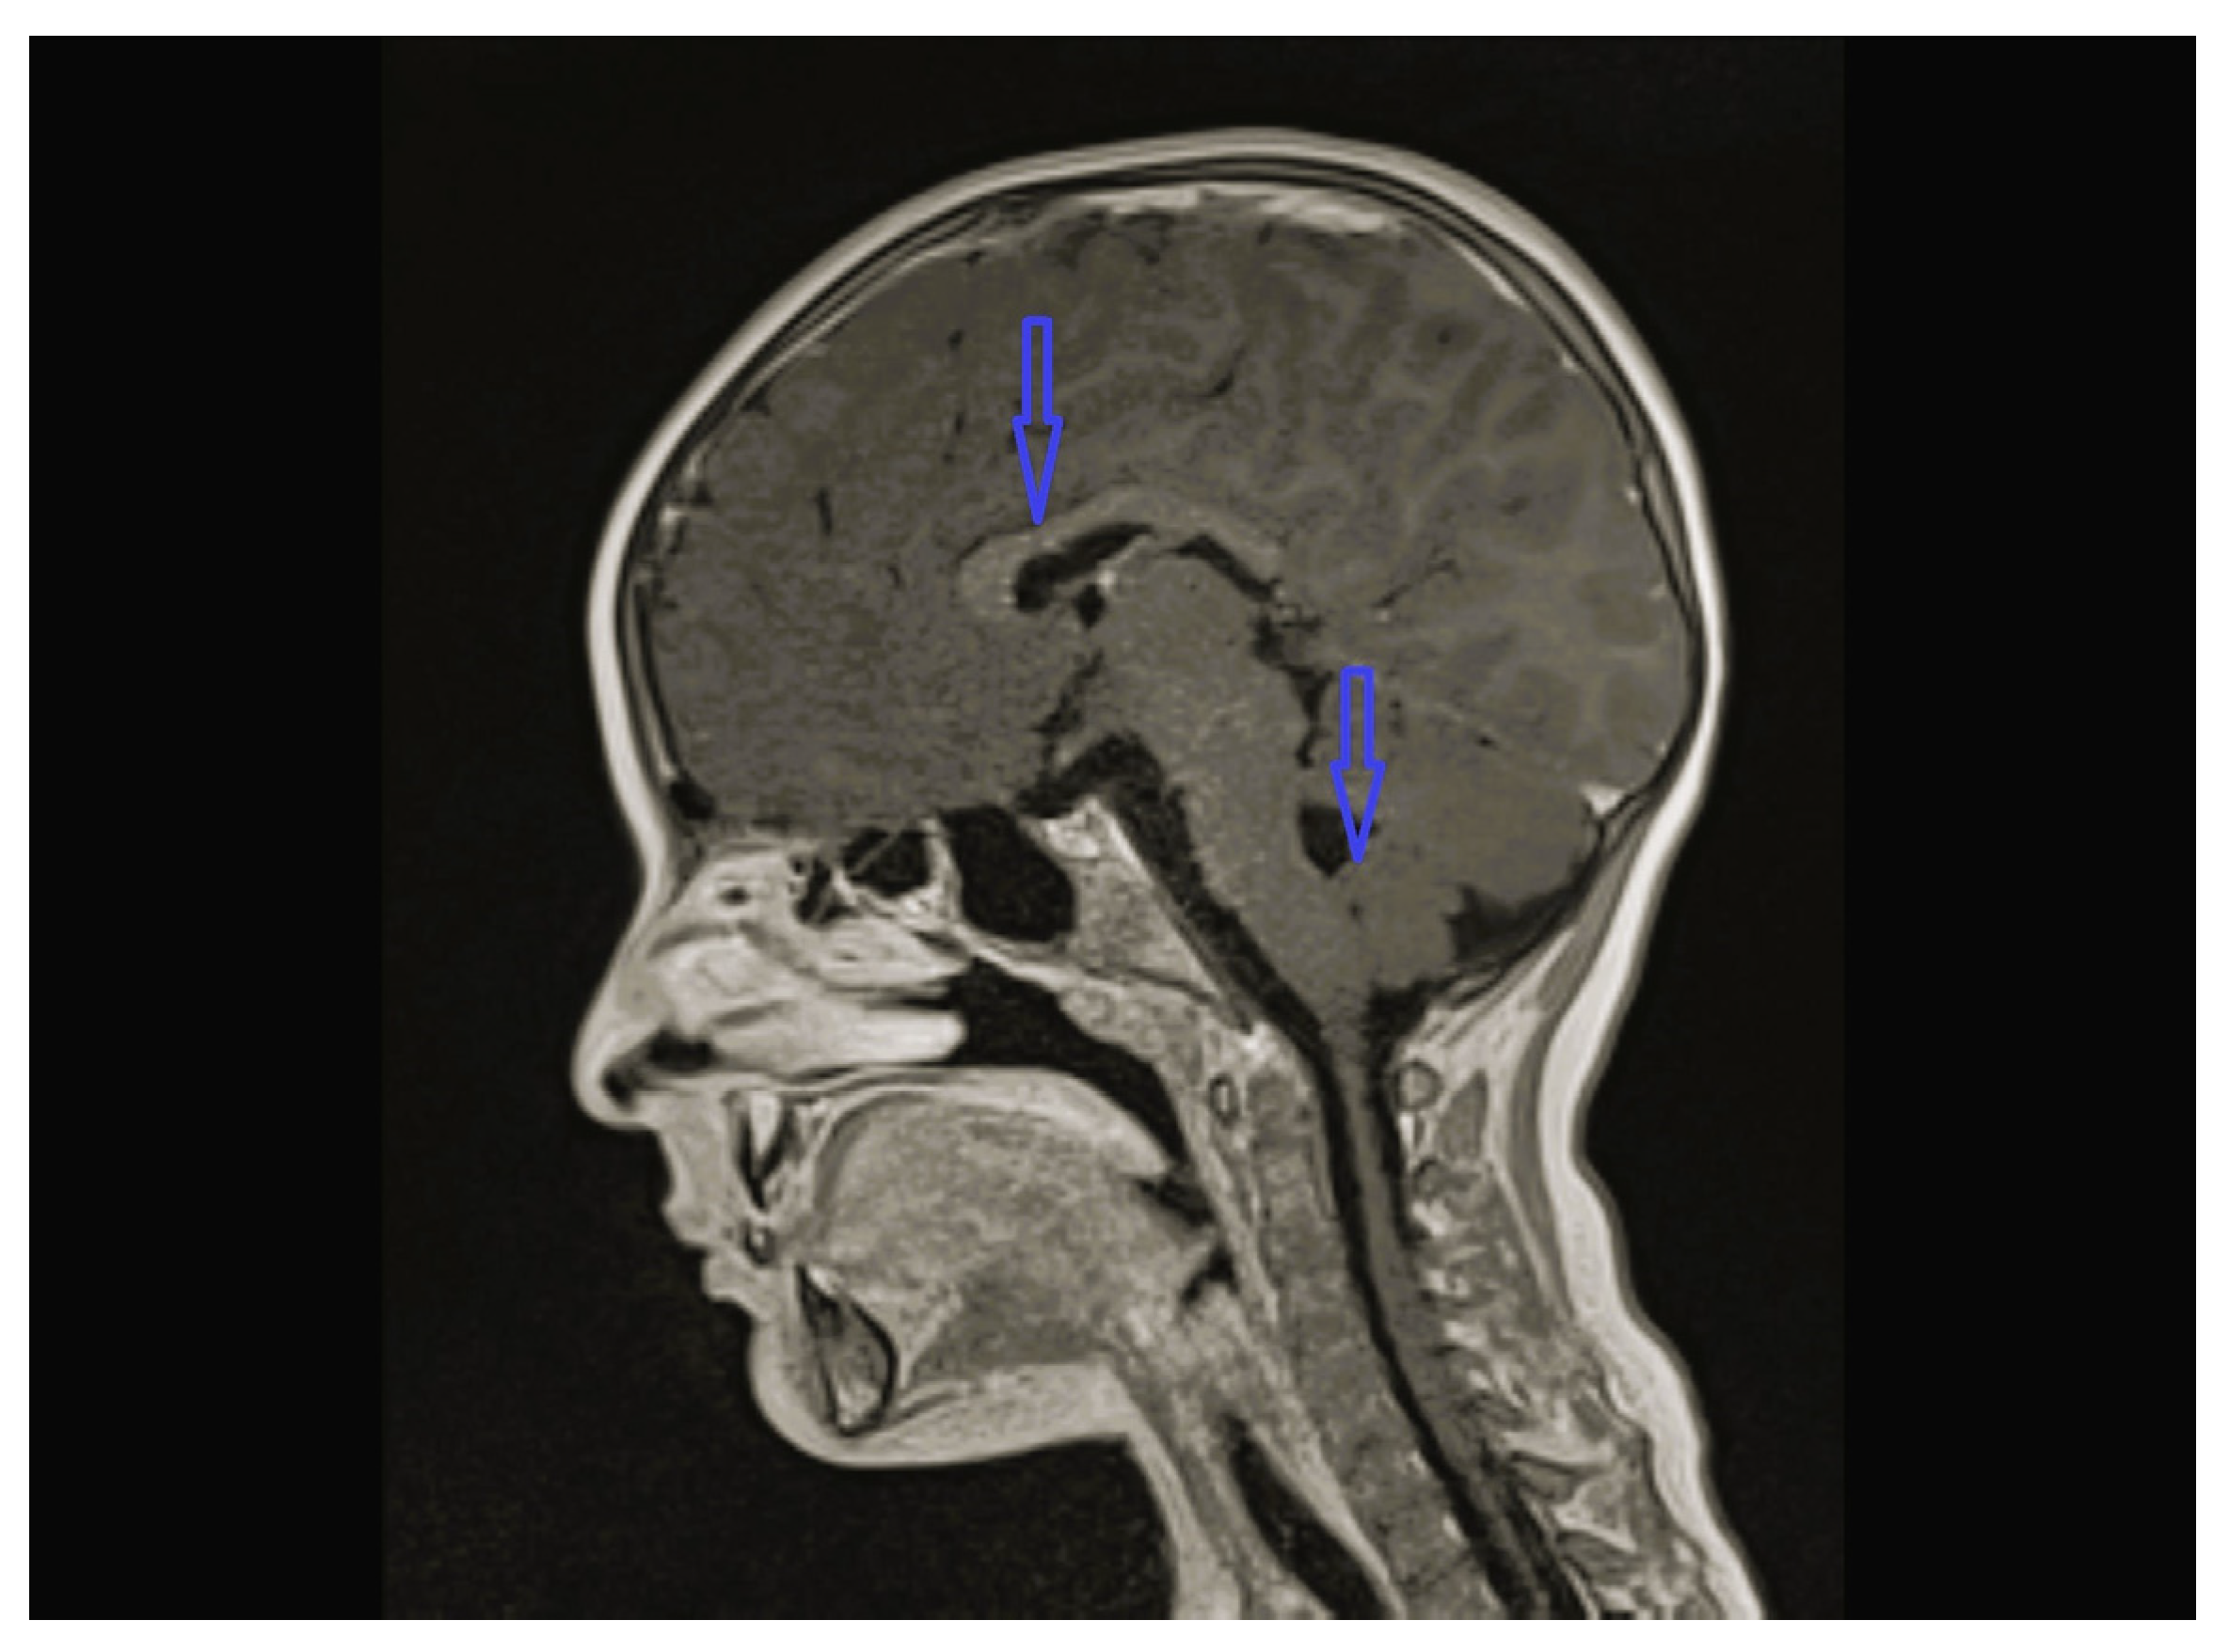

| 1 | - | - | - | Cerebellar hypoplasia, vermis dysplasia and corpus callosum (CC) hypoplasia | Normal | SPG11 c.6730C>T heterozygote (p.L2244F) | Physical therapy |

| 8 | Normal | - | Multifocal spike and waves pattern | Vermian, CC and brainstem hypoplasia | Normal | KIDINS220 NM_020738.4 c.4388C>A heterozygote p.S1463* | Physical therapy, clonazepam, sodium valproate |